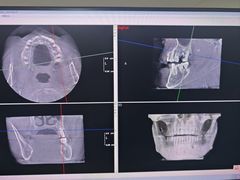

• 土豆口腔(凤凰北总店)

• -土豆口腔(凤凰北总店)